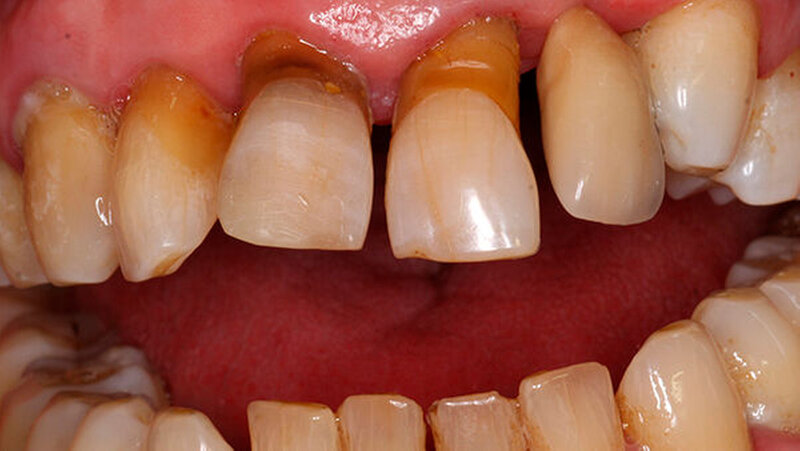

Ein 80 Jahre alter Patient stellt sich im September 2016 in der Poliklinik mit der Bitte um festsitzende Versorgung der Frontzahnlücke in Regio 22 vor (Abbildungen 1 und 2) Der Zahn 22 musste vor etwa einem Jahr parodontal bedingt extrahiert werden. Seitdem war diese Lücke durch einen Interimsersatz versorgt. Nach klinischer und röntgenologischer Befundung stellt sich schnell die Problematik dar, die im Rahmen der Versorgung dieser Frontzahnlücke auftreten wird.

Die Versorgung der Frontzahnlücke in Regio 22 wird intensiv mit dem Patienten diskutiert. Aufgrund des absoluten Mangels an ortsständigem Knochen, des hohen Patientenalters sowie der eher mäßigen Mundhygiene scheidet eine Implantation mit Knochenaugmentation aus. Hinzu tritt die starke, vor allem im Frontzahngebiet ausgeprägte Parodontitis. Ein langfristiger Erhalt des endodontisch versorgten 11 sowie des stark parodontal kompromittierten 21 erscheint unrealistisch.

Für eine konventionelle brückenprothetische Versorgung scheiden die Schneidezähne ebenfalls aus: Zum langfristig prognostisch sicheren Ersatz des 22 wären Extraktionen und mehrere Substanz-opfernde Präparationen unausweichlich. Aufgrund des hohen Patientenalters und des Ausscheidens klassischer prothetischer Rehabilitationsmaßnahmen wird die Frontzahnlücke mit einer Adhäsivbrücke aus Metallkeramik versorgt (Abbildungen 3 und 4).